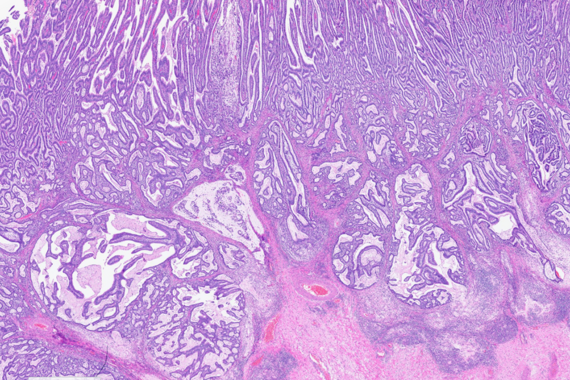

Gastric biopsies in a 43-year-old female, following Helicobacter pylori eradication.